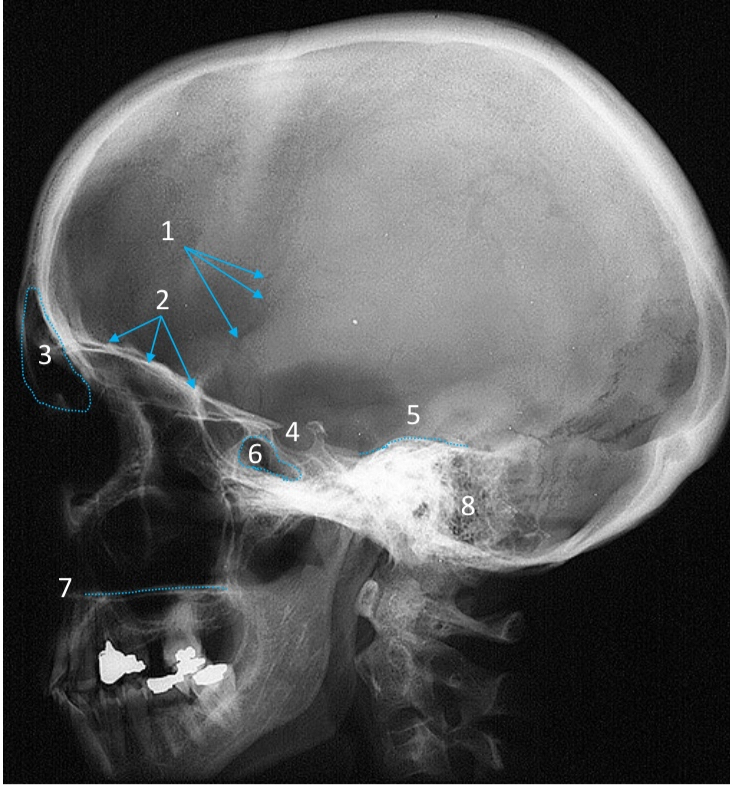

Mandible

ID bone

Maxilla

ID bone

Frontal sinus

ID structure

Pituitary fossa

ID structure

Occipital

ID bone

Lambdoid suture

ID structure

Frontal sinus

ID structure

Orbital margin

Orbit

Maxillary sinus

ID structure

Mandibular condyle

ID structure

Inferior nasal concha

ID structure

Hard palate

ID strucutre

Gonial angle

ID strucutre

Petrous ridge

ID structure

Groove of middle meningeal a.

ID structure

Roof of orbit

ID structure

Frontal sinus

ID structure

Pituitary fossa

ID structure

Petrous ridge

ID structure

Sphenoid sinus

ID structure

Hard palate

ID structure

Mastoid air cells

ID structure

Zygomatic arch

ID structure

Mandibular condyle

ID structure

External auditory meatus

ID structure

Mastoid air cells

ID structure

Foramen magnum

ID structure

Foramen ovale

ID structure

Foramen spinosum

ID structure